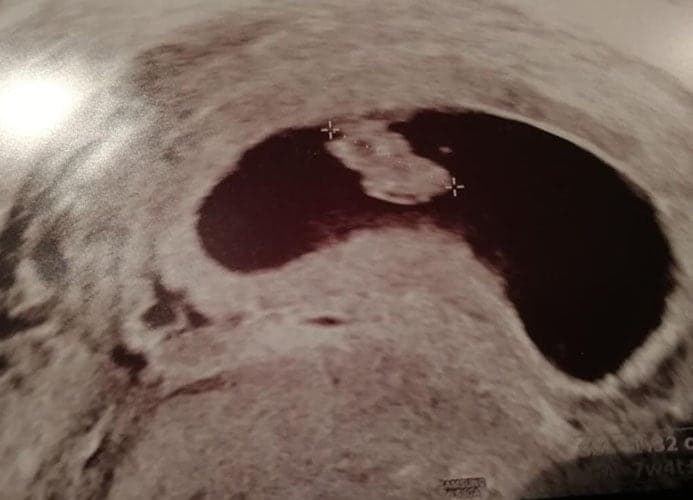

Ultraschallbilder aus dem 1. Trimester (1. SSW bis 12. SSW)

Im ersten Trimester sind die Ultraschallbilder meist noch schwer zu deuten. Oft erkennt man in den letzen Wochen des ersten Trimesters gut den Körper, den Kopf und die Gliedmaße. Das Geschlecht kann man in dieser Zeit meist noch nicht erkennen.